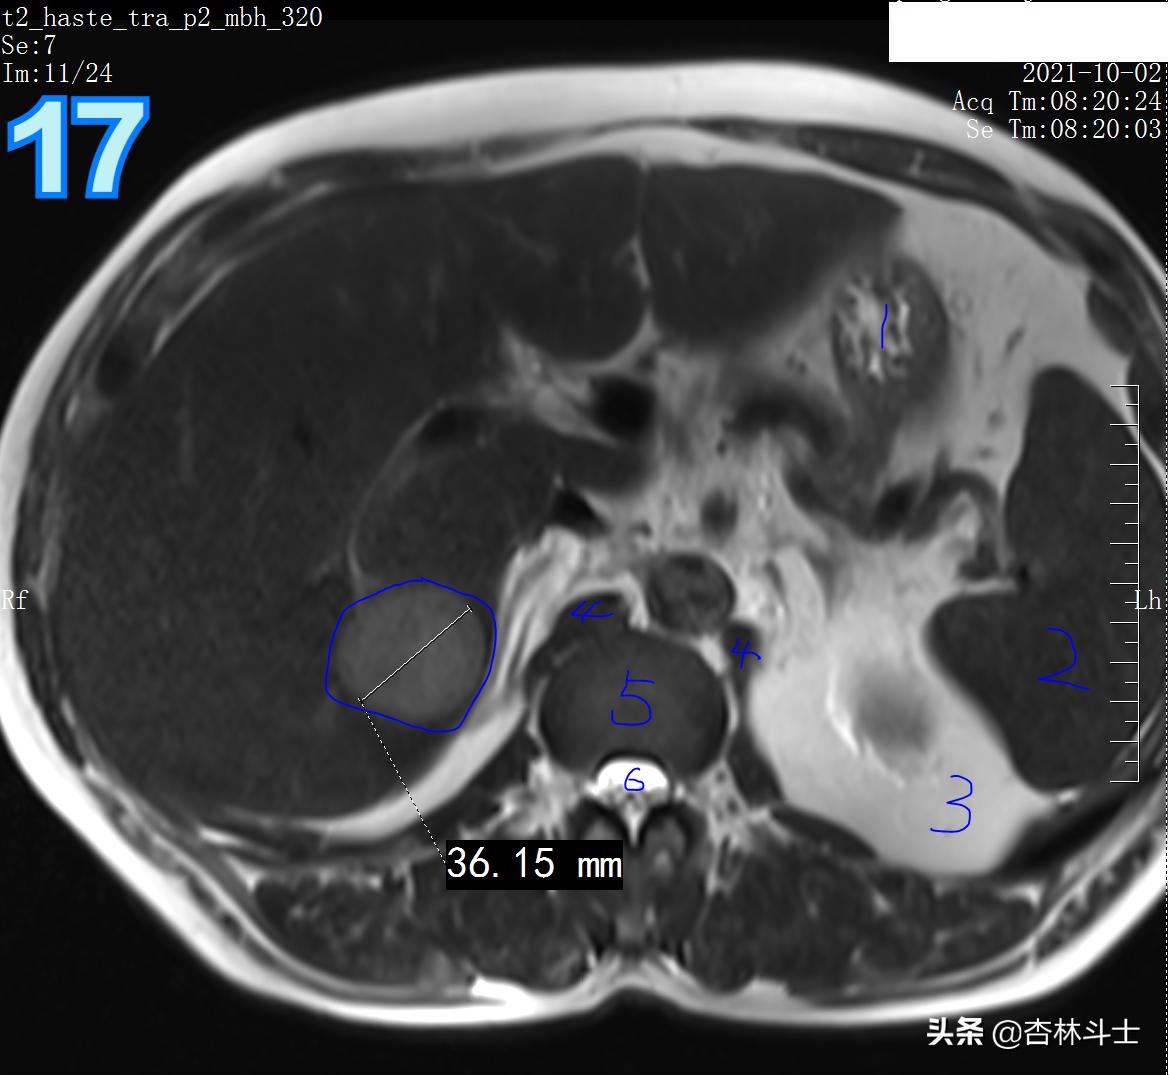

T2

图17 1、胃 2、脾 3、左肾肾周脂肪 4、双侧膈肌脚 5、椎间盘 6、椎管

T2压脂

图18 1、皮下脂肪 2、肝内胆管 3、肝内门静脉分支 4、胃 5、腹主动脉 6、下腔静脉 7 椎体 8、椎管 9、脊髓 10 脾